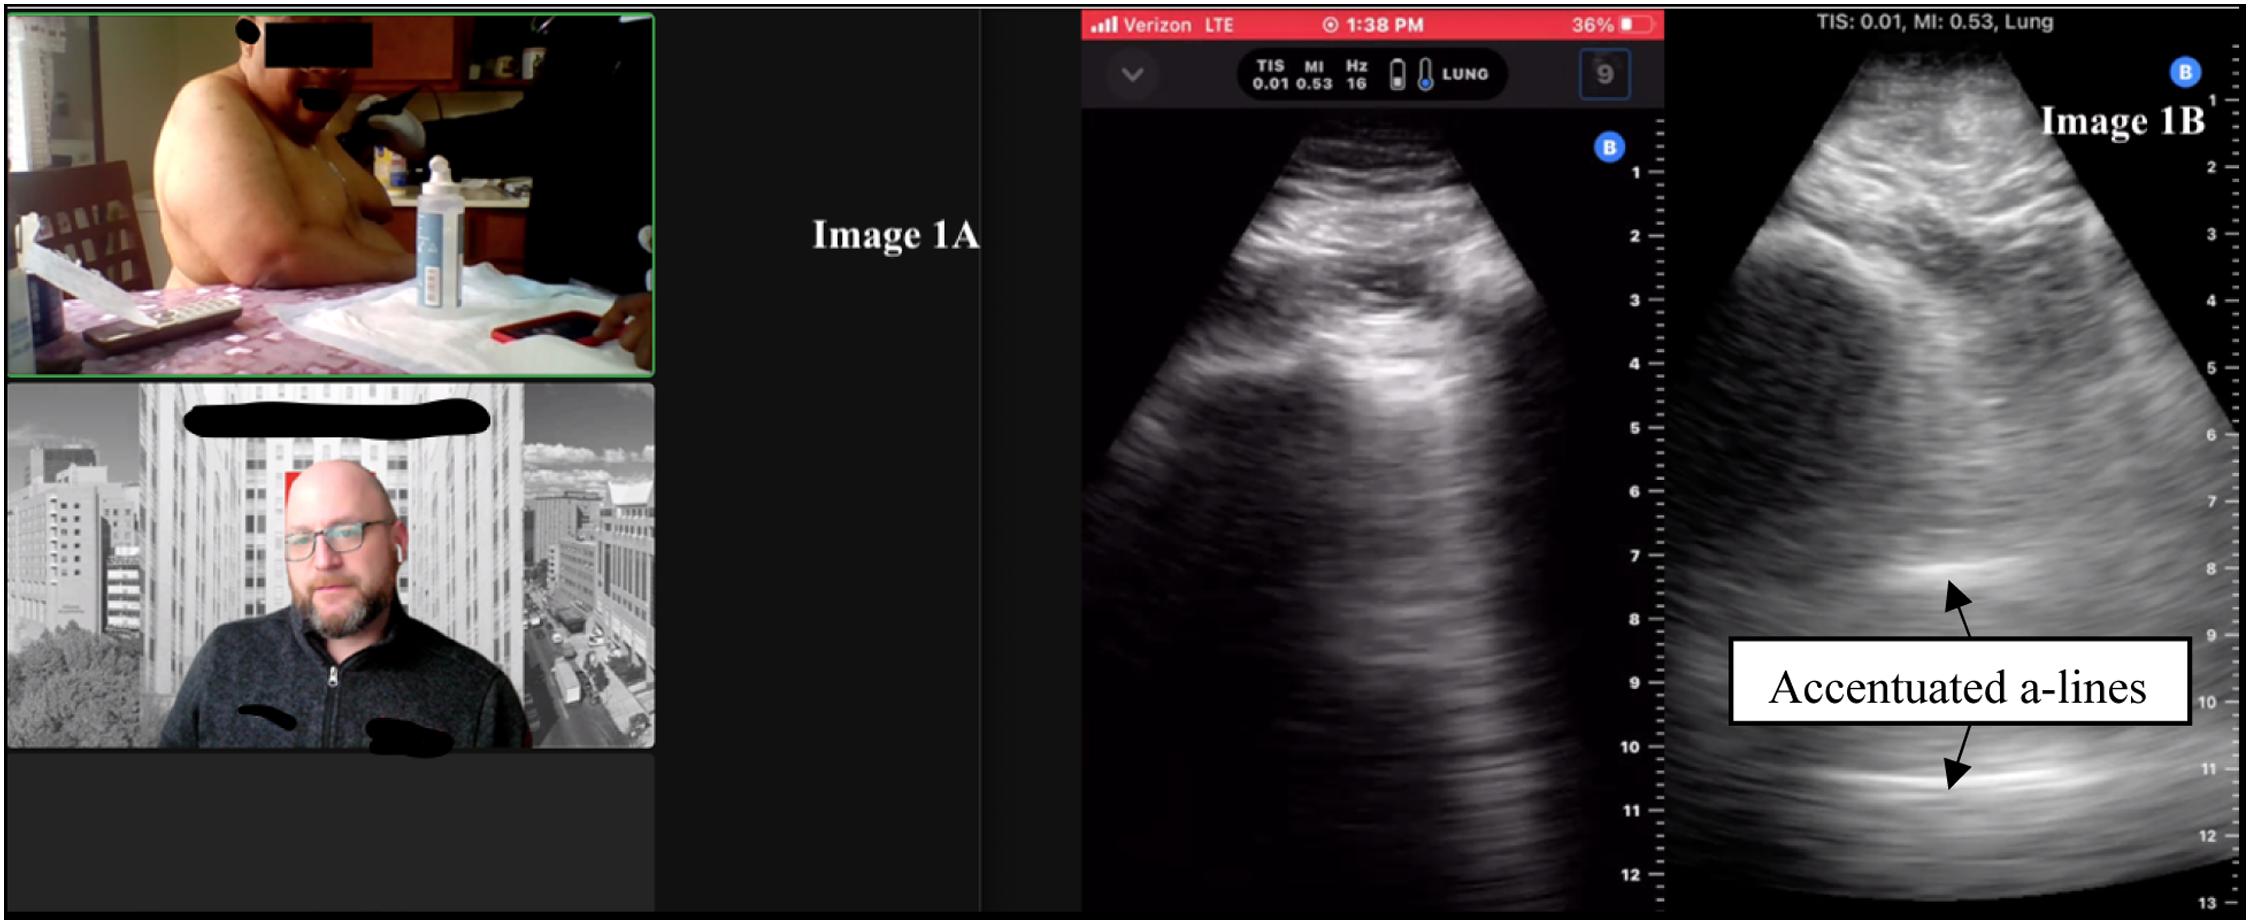

Duringhisinitialevaluationbyparamedicshedenied othercomplaints.Initialvitalswerepulse65beatsper minute,bloodpressure122/77millimetersofmercury,pulse oximetry100%onroomair,temperature36.6° Celsius,and respirations19breathsperminute.Hisphysicalexamwas significantforlethargy,althoughhewaseasilyarousableto voice;left-sidedchestwalltendernesstopalpation;bruising; crepitus;decreasedleftbreathsounds;andbilaterallower extremitypittingedema.Paramedicsobtainedbilateral anteriorviewsofthelung(Image1a),andimageswere interpretedinreal-timebythephysicianviaavideo

telehealthplatform.TheEPnotedtheabsenceoflungsliding intheleftinferiorlung field(Image1b).

Thepatientwasplacedon100%oxygenvianonrebreathermaskandtransportedtoalocalemergency department(ED).UponarrivalattheEDhedeniednew complaints,andhisvitalsandphysicalexamwerenot significantlychanged.Hiselectrocardiogram(ECG)showed anatrialsensedpacedrhythmconsistentwithpriorECGs. Hehadachestradiograph(CXR)showingleft fifthandsixth ribfractureswithamoderatecircumferentialpneumothorax (Images2 and 3).

Image1. (A)Exampleofacommunitytele-paramedicvisitwithvideoconferenceandscreensharingusingmobileultrasound.Thepatientis seenatthetop,andtheemergencyphysicianisseenonthebottomscreen.(B)Thecasepatient’sb-modelungpoint-of-careultrasound, showingaccentuateda-lines,lossofb-lines,andinreal-timevideowithoutlungsliding(notpicturedhere).

Image2. Chestradiographwitharrowspointingtoleft-sidedmoderatecircumferentialpneumothorax.Thereisalossofsymmetry,avisible lungborder,andlossoflungmarkingsuperiortothelungborder.